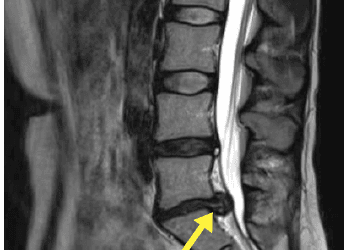

This image is an MRI of a patient’s lumbar spine (lower back), showing a significant disc bulge. You can see the disc...